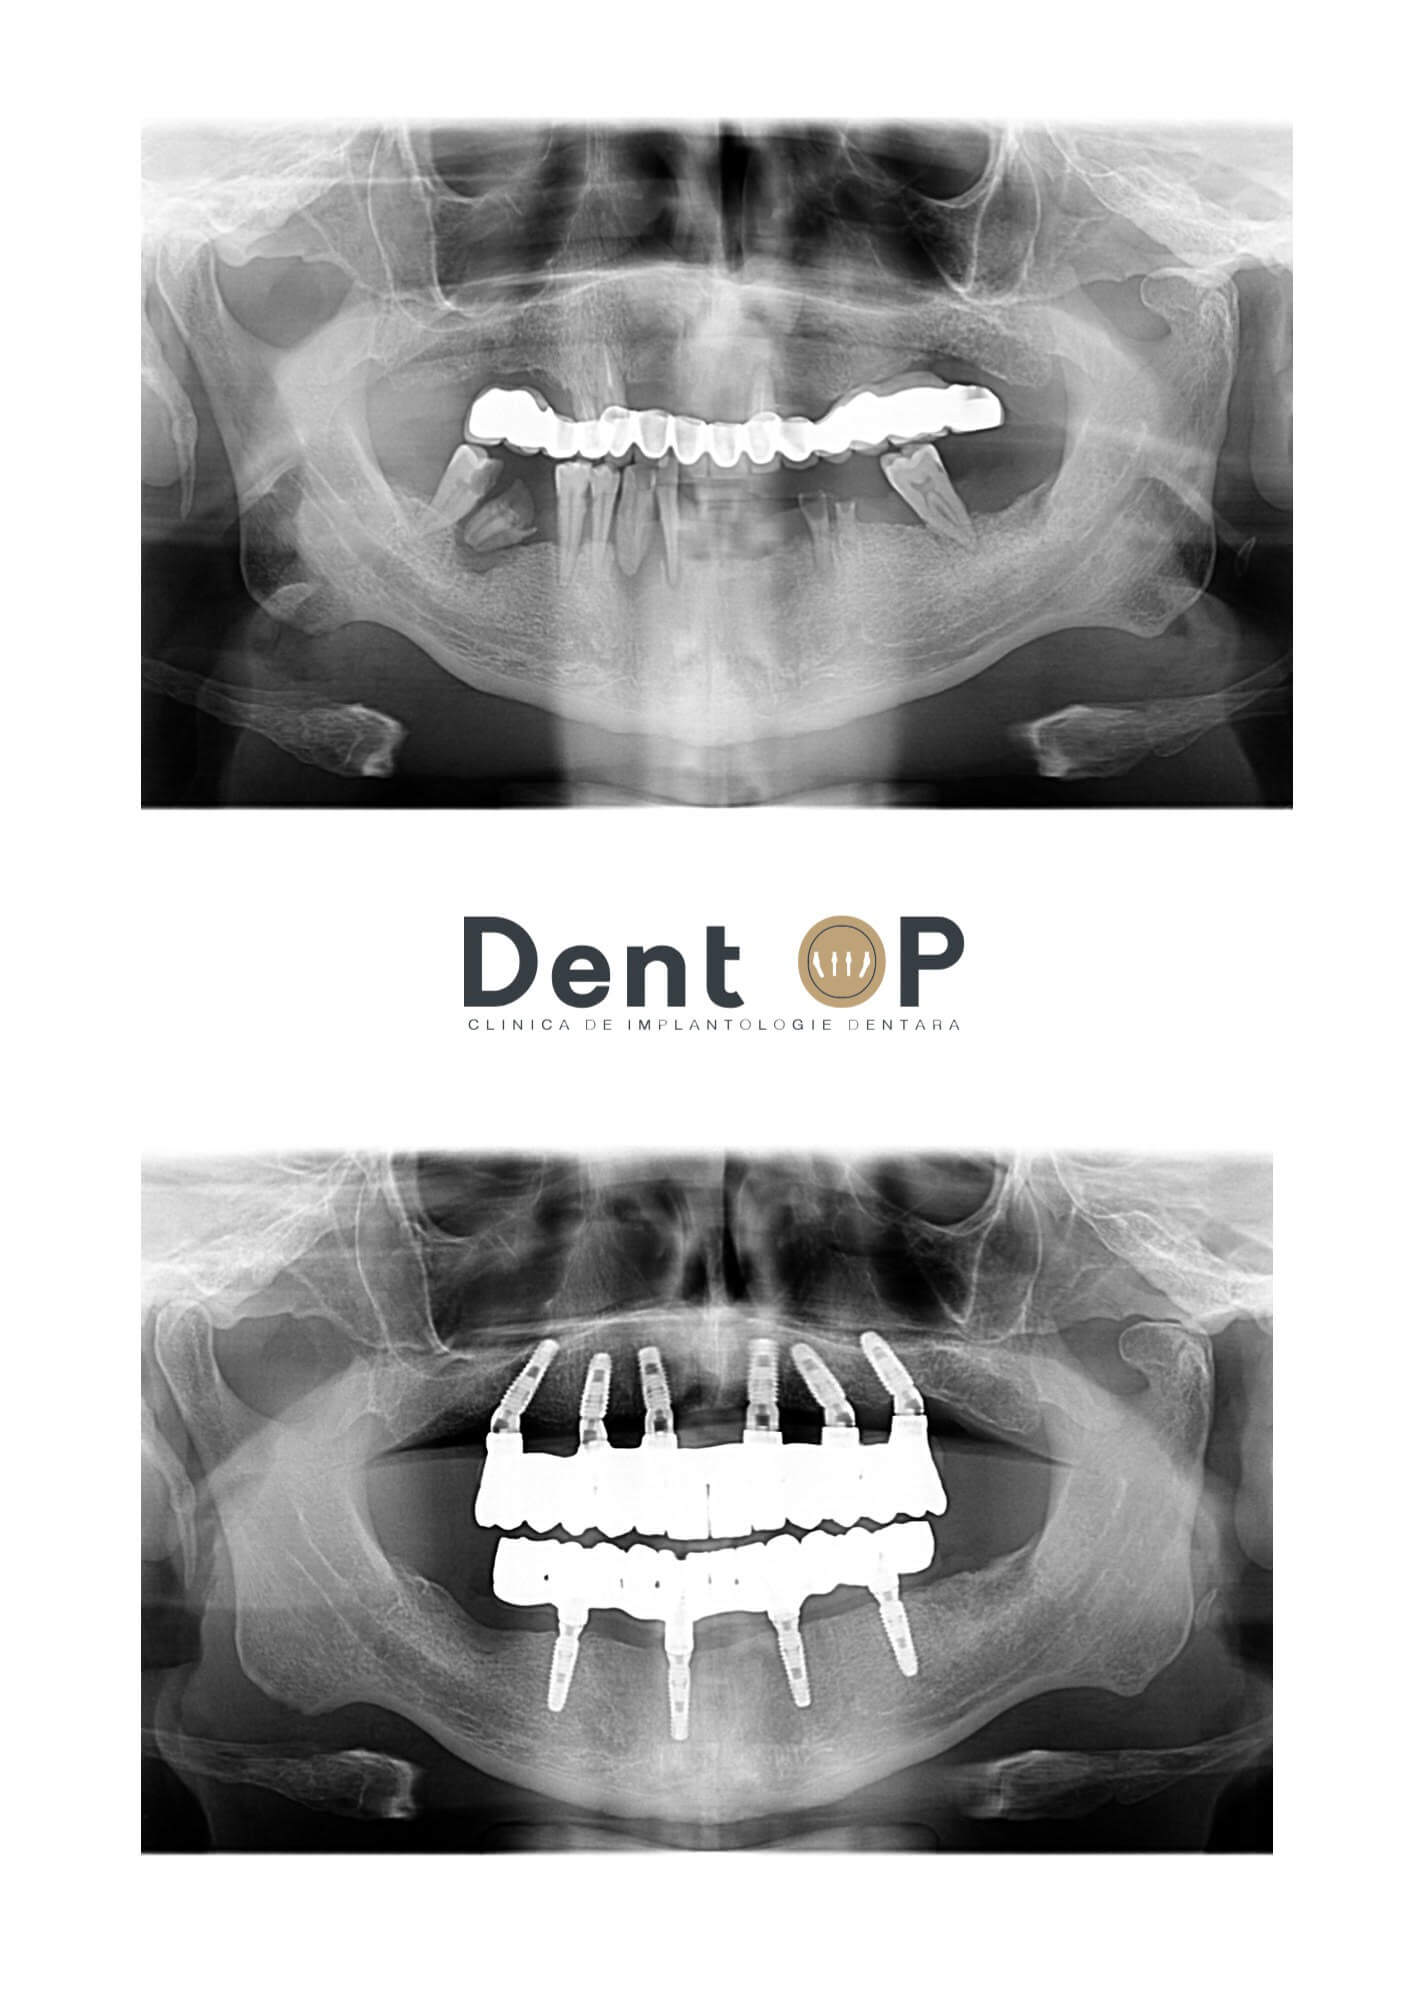

Domnul P. s-a prezentat cu o lucrare foarte veche care abia se mai ținea pe 3 dinți rămași. În cadrul consultației, Dr Cazacu Corrado a observat și infecții cauzate de boala parodontală care au afectat în mod special zona mandibulei.

Planul de tratament indicat de Dr Cazacu Corrado a fost procedura ,,Dantură Fixă în 24h pe implanturi dentare” cu reabilitarea atât a maxilarului, cât și a mandibulei într-o singură ședință cu Sedare Conștientă.

I-au fost inserate 10 implanturi dentare într-o singură ședință, numai după ce infecțiile cauzate de boala parodontală au fost curățate în întregime de către Medicul Specialist Parodontolog.